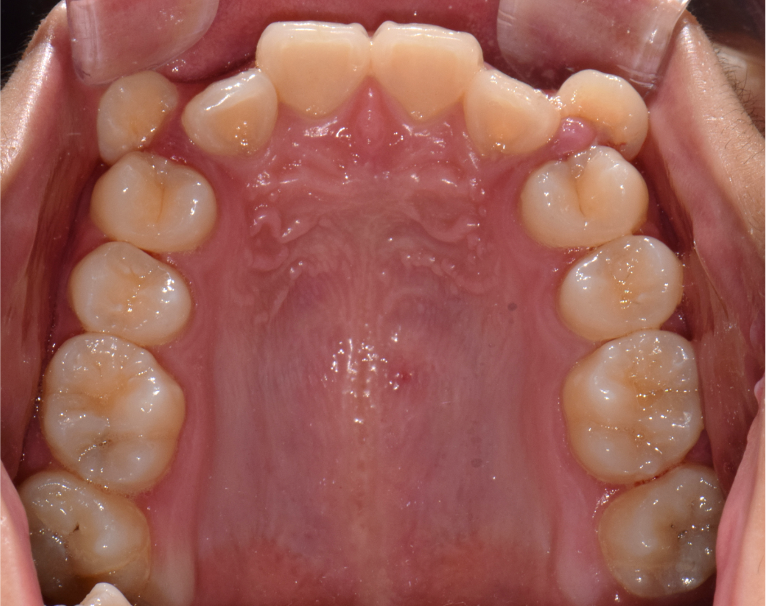

상악 악궁이 좁을 경우에는 하악을 편안하고, 안정적으로 수용하지 못하기 때문에 치아의 배열이 고르지 못하고, 이로 인해 돌출입, 주걱턱과 같은 문제가 생기게 됩니다. 이러한 경우 악궁확장을 통해 미리 증상을 예방하거나 이미 문제가 발생한 경우 시행하여 안정적이고, 바른 치아배열을 만들 수 있습니다. 아래사진은 주걱턱 개선을 위해 양악 수술을 할 줄 알고 큰 근심을 가진 환자를 상악궁 확장을 통한 비수술-비발치 교정으로 치료한 증례입니다.

좁은 악궁을 가진 케이스